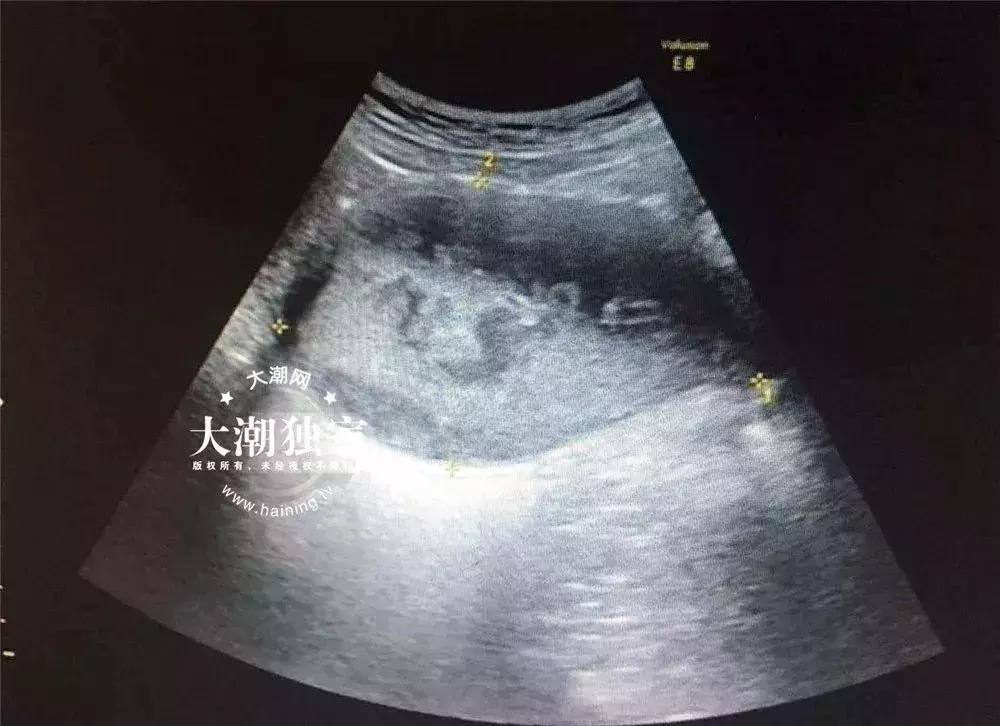

接诊的医生询问了小燕的病情后,当场就觉得小燕的情况有些特别,于是马上给小燕安排了B超和妇科检查。

△小燕的B超报告

根据检查,医院妇科主任俞丽娟判断,小燕得了处女膜闭锁伴盆腔感染!需要马上住院进行手术治疗。